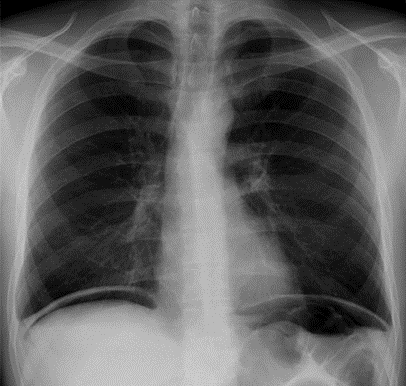

Pleural Effusion

____ is defined as the accumulation of fluid in the pleural space.

____ is seen in the costophrenic angle only (seen on Lat. views), unless it is a high level ___ (Lat. and PA views).